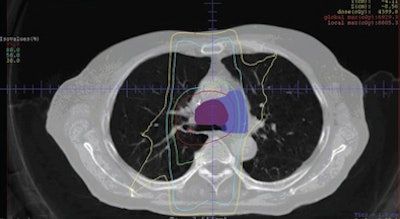

| Images are of a 62-year-old man with NSCLC. Initial pre-FDG-PET and clinical target volume (CTV) are represented in blue and red, respectively, on frontal (above) and transverse (below) images. FDG-PET images resulted in a decrease of mediastinal CTV and treated volume. Isodose lines represent dose distribution (95%, 80%, 50%, and 30% of prescribed dose). Images courtesy of the American Journal of Roentgenology. |